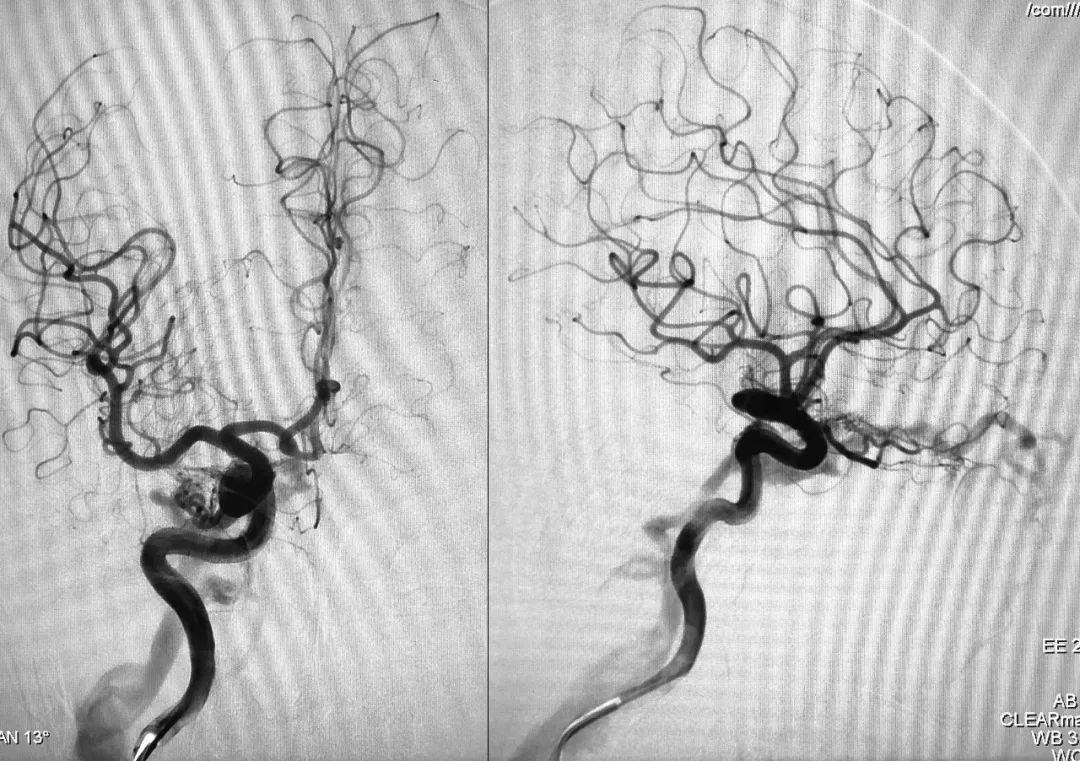

⑧ 术后左侧颈总动脉造影显示瘘口不显影:

将造影管移入右侧颈总动脉,正、侧位造影显示瘘口不显影:

正、侧位蒙片显示Onyx-18胶在右侧海绵窦内的铸型(约4.5 mm):

⑦ 术后左颈总动脉正、侧位造影显示瘘口不显影:

术后正、侧位蒙片显示伊维尔-Ⅰ胶在右侧海绵窦内的铸型(约6 ml):